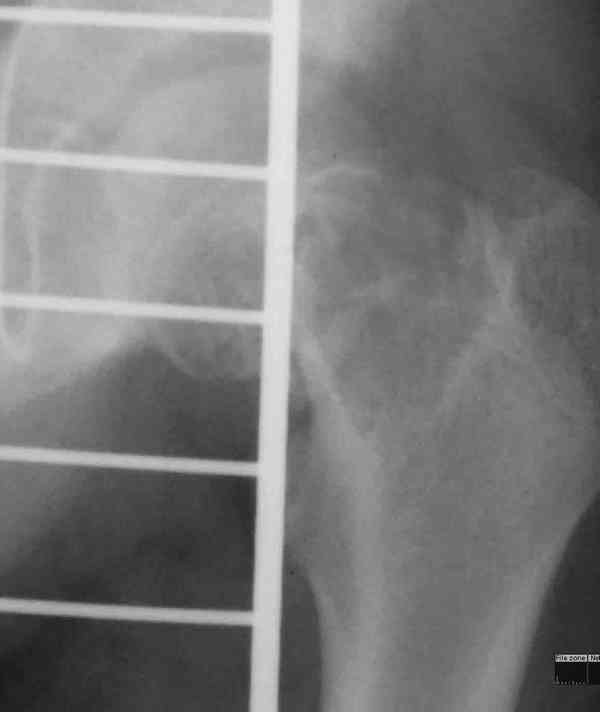

Около 16 лет наблюдаю пациента с ФИБРОЗНОЙ ДИСПЛАЗИЕЙ левой нижней конечности, полиосальная форма. Прилагаю рентгенснимки.

Рекомендую консультироваться в Европейском Центре Фиброзной дисплазии - город Лион, Франция. Они там зубы на этом сьели.